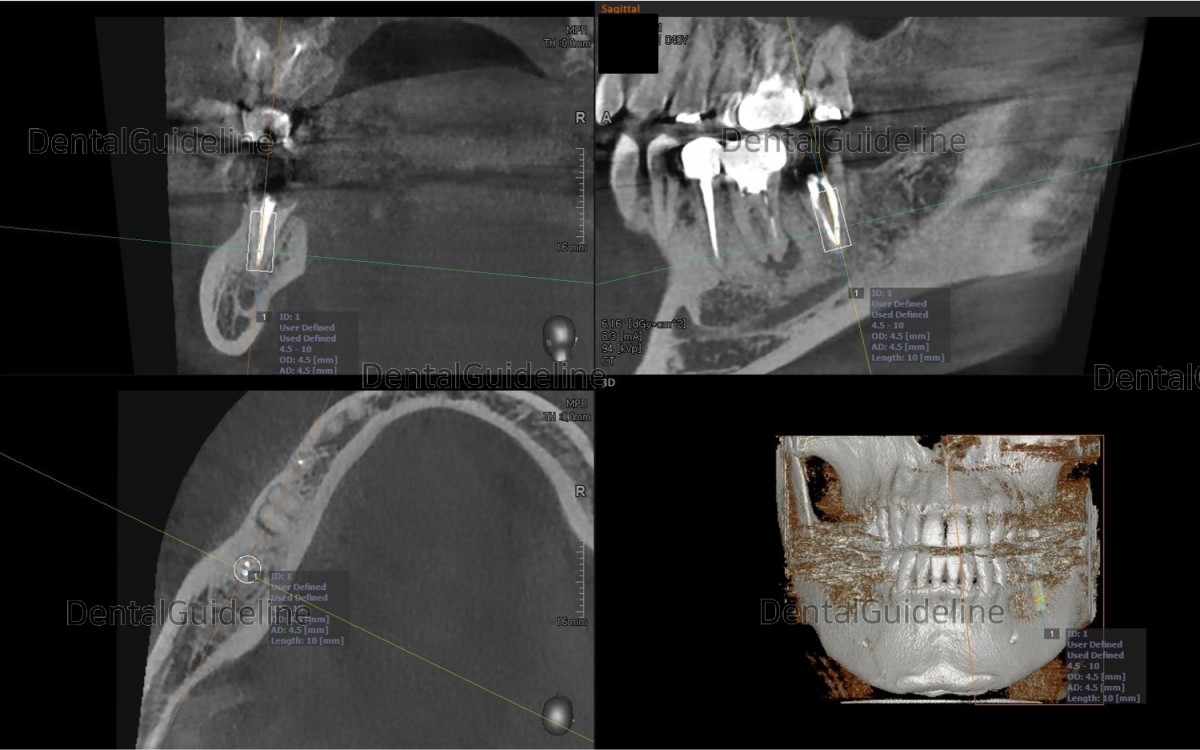

Rough simulation on the CBCT scan views The socket size of the 1st molar didn’t seem to accept the immediate placement of an implant It seems hard to get initial stability.

After serial drilling, an Arum Dentistry® Ø4.5/L10mm-sized implant was placed in the 2nd molar zone and had good initial stability(45Ncm).

All the existing granulation tissue was removed and an Arum Dentistry® Ø4.5/L10mm-sized implant was placed. The implant in the 1st molar zone also had relatively good initial stability(25Ncm).